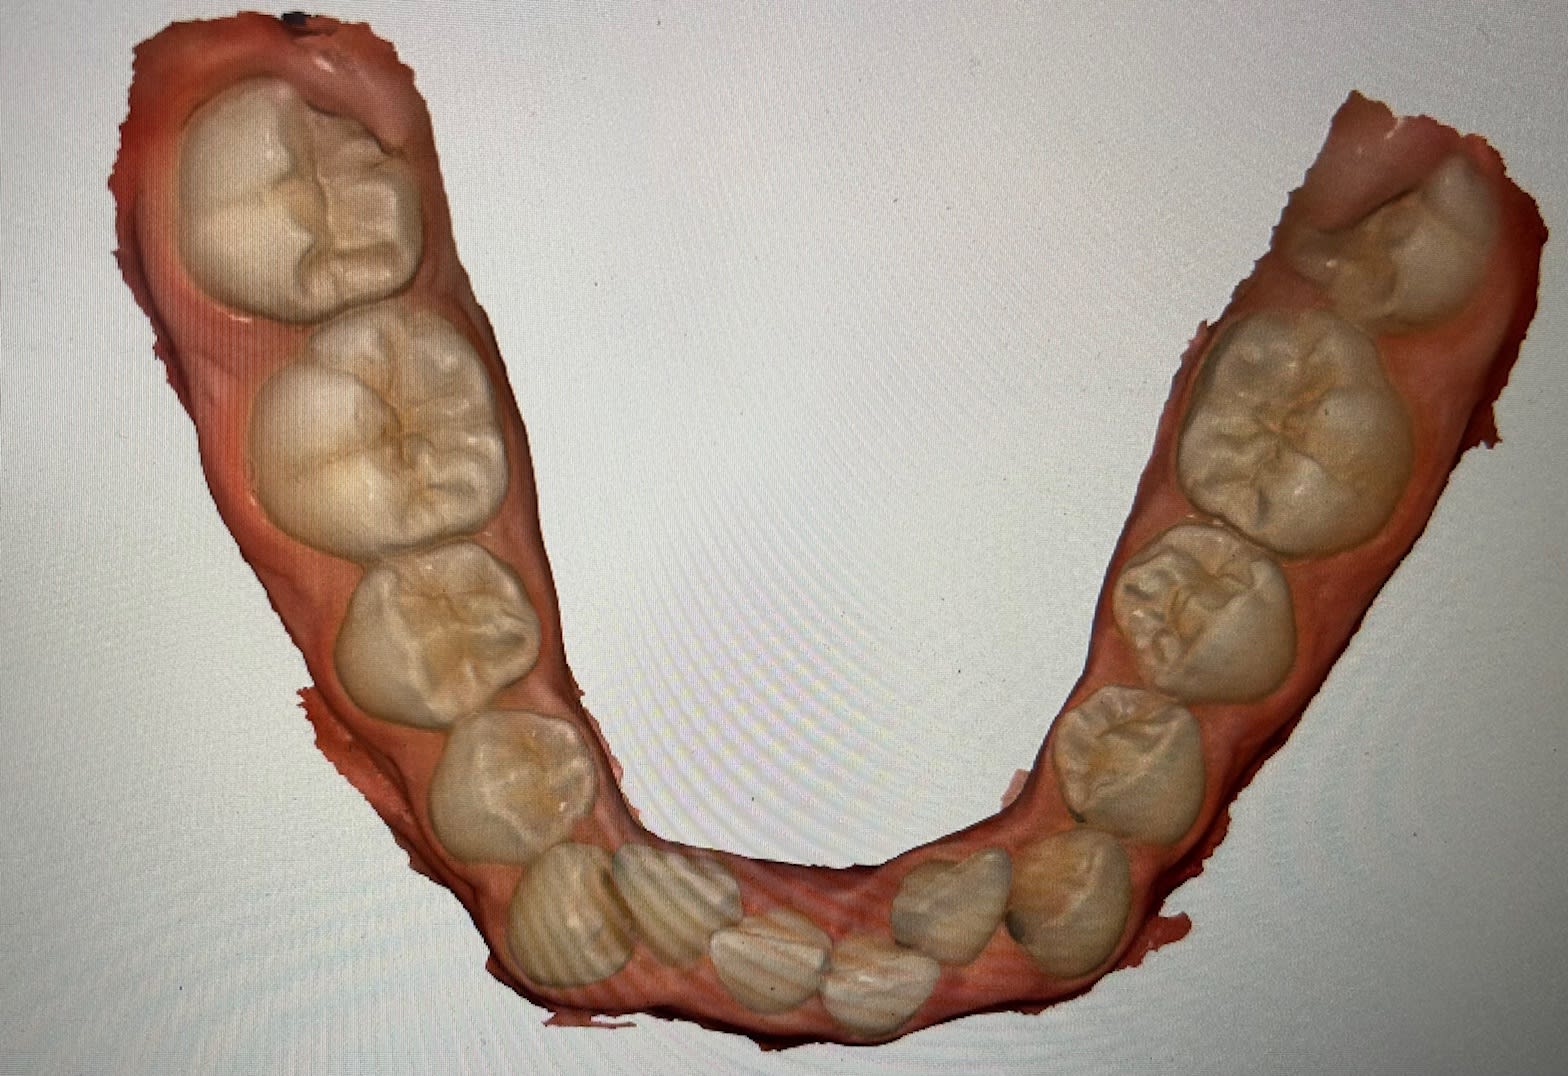

Jeune fille de 11 ans et demi, hypodivergente tendance classe III squelettique (mais classe II dentaire) et biretroalveolie. Agénésie de 12 avec évolution de 13 à sa place et 22 rhyziforme.

On peut avoir une photo mandibulaire vue du dessus ?

Voir le bas, le niveau d'encombrement.

Pas de vue occlusal mand ? Ouvre medit link et sors nous une vue occlusale. Ne surtout pas extraire une incisive mandibulaire. Tu vas augmenter la supraclusion et créer un overjet.

Au temps pour moi, les voici ce n'étaient pas passé lors du téléchargement du post et je n'avais pas vu...

Et oui n'extrait pas en bas à la vue de ta photo mandibulaire stp et la supra actuelle.